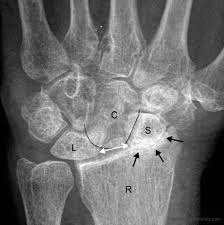

These are some of the main ligaments in the wrist.  These ligaments hold the small bones of the wrist together to themselves and to the end of the radius and ulna.  These ligaments serve a very important function for the wrist.  When these ligaments are injured they can cause significan dysfunction to the wrist.